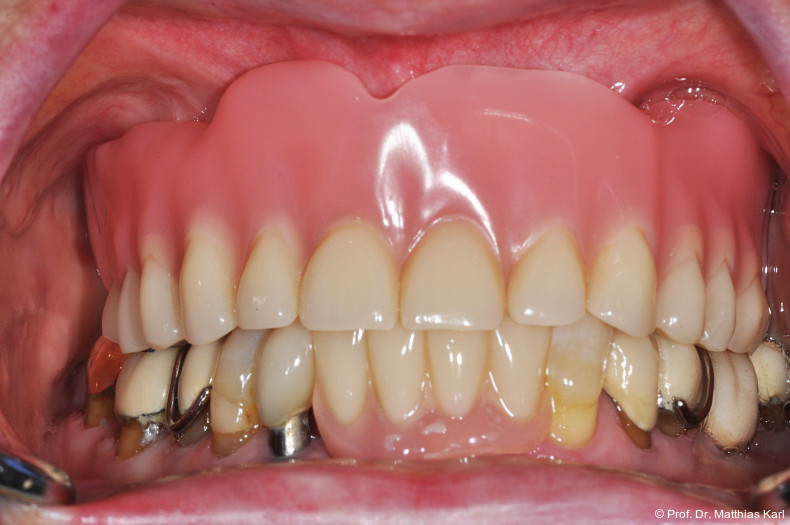

Die Insertion von zwei zahnärztlichen Implantaten zur Verankerung einer abnehmbaren Deckprothese stellt eine kosteneffektive Therapie dar, welche die Kaufunktion verbessert und zu hoher Patientenzufriedenheit führt, weshalb diese Versorgung in mehreren Ländern als „standard of care“ angesehen wird.1, 6, 14 Die dabei genutzten Verankerungselemente, welche die Prothese mit den Implantaten abnehmbar verbinden, sind entscheidend für den Prothesenhalt, die Patientenzufriedenheit und den klinischen Erfolg.14 Stege, Kugelkopf­anker und Locatoren werden hierfür häufig genutzt und führen zu einer Verbesserung der mundbezogenen Lebensqualität.4–6, 14 Die in Deutschland weitverbreiteten Doppelkronensysteme konterkarieren aufgrund der hohen Herstellungskosten die Grundidee einer kosteneffektiven Grundversorgung.8, 10, 15

Insgesamt 13 zahnärztliche und zahntechnische Kolleg/-innen beantworteten eine im Rahmen der IDS 2025 durchgeführte allgemeine Umfrage zu Attachmentsystemen für implantatgetragene Deckprothesen, wobei Mehrfachnennungen möglich waren. Der Retentionsverlust wurde dabei als häufigstes Problem beschrieben, gefolgt von der Notwendigkeit spezieller und systemspezifischer Instrumente. Dies deckt sich mit den Ergebnissen aus der Literatur, welche Retentionsverlust als die wesentliche Komplikation nennen. Die Lebensdauer von Kunststoff-Retentionseinsätzen wurde in weiter Streuung mit unter drei bis zu 24 Monaten angegeben. Diese Spanne lässt sich durch unterschiedliche Grade an Parallelität der unterstützenden Implantate erklären. Als wünschenswert für Attachmentsysteme wurden folgerichtig die Fähigkeit zur Kompensation nicht paralleler Implantate sowie eine längere Lebensdauer der Retentionseinsätze erwähnt.